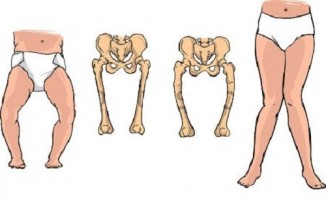

ხალხური მედიცინის საშუალებები რაქიტის თავიდან ასაცილებლად და სამკურნალოდ

რაქიტი - ორგანიზმის საერთო დაავდებაა, რომელსაც " ინგლისურ ავადმყოფობას " უწოდებენ; გამოწვეულია D ვიტამინისა და მზის სხივების უკმარისობით, იწვევს..